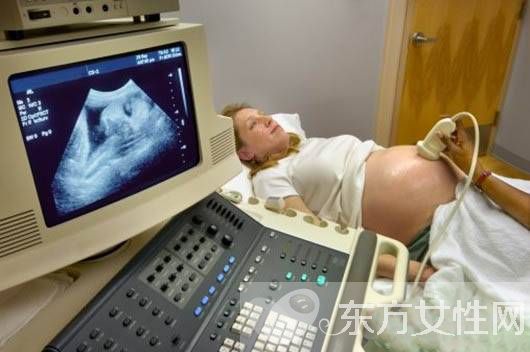

第二次B超检查时间为20-26周,此时期为排畸检查,一般采用三维或四维彩超进行,能检出绝大多数的胎儿畸形,如颜面部、四肢、大脑、内脏器官、心脏畸形等。

第三次B超检查时间为30-32周,作用为补充排畸及胎儿生长发育情况的检查,查验胎儿是否有生长受限、羊水及脐带情况等。

第四、五次B超检查分别在孕第37、39周,作用相同,均为检查胎盘成熟度、胎儿生长发育情况,不涉及胎儿结构检查。此时期如果脐带无绕颈现象,则选择黑白B超即可,如果发生了脐带绕颈现象,医生会建议选用彩超来做脐动脉血流检查。